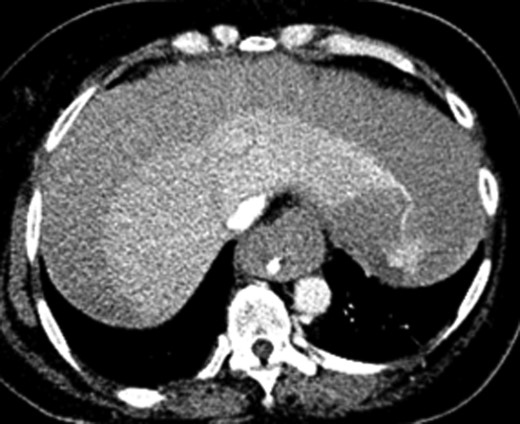

A 61-year-old female initially presented to the emergency department with shortness of breath and back pain. The patient had recently traveled to Haiti and made several trips to Denver by car. She was initially alert and oriented but sustained a cardiac arrest shortly after arrival and underwent CPR for pulseless electrical activity (PEA). Approximately 5 min into resuscitative efforts, a LUCAS 2.0 (Physio-Control Inc., Lund, Sweden) device was placed for continued chest compressions for 30 min. Bedside echocardiogram showed a dilated RV with a suspected massive PE and the ECMO team was activated. The patient was intubated and VA-ECMO access was obtained through the left femoral artery and right common femoral vein under ultrasound guidance with 17 Fr arterial and 25 Fr venous cannulas (Fig. 1). After a total of 35 min of CPR, the patient had spontaneous return of circulation.

Abdominal x-ray of VA-ECMO cannulation within the IVC and left iliac artery.